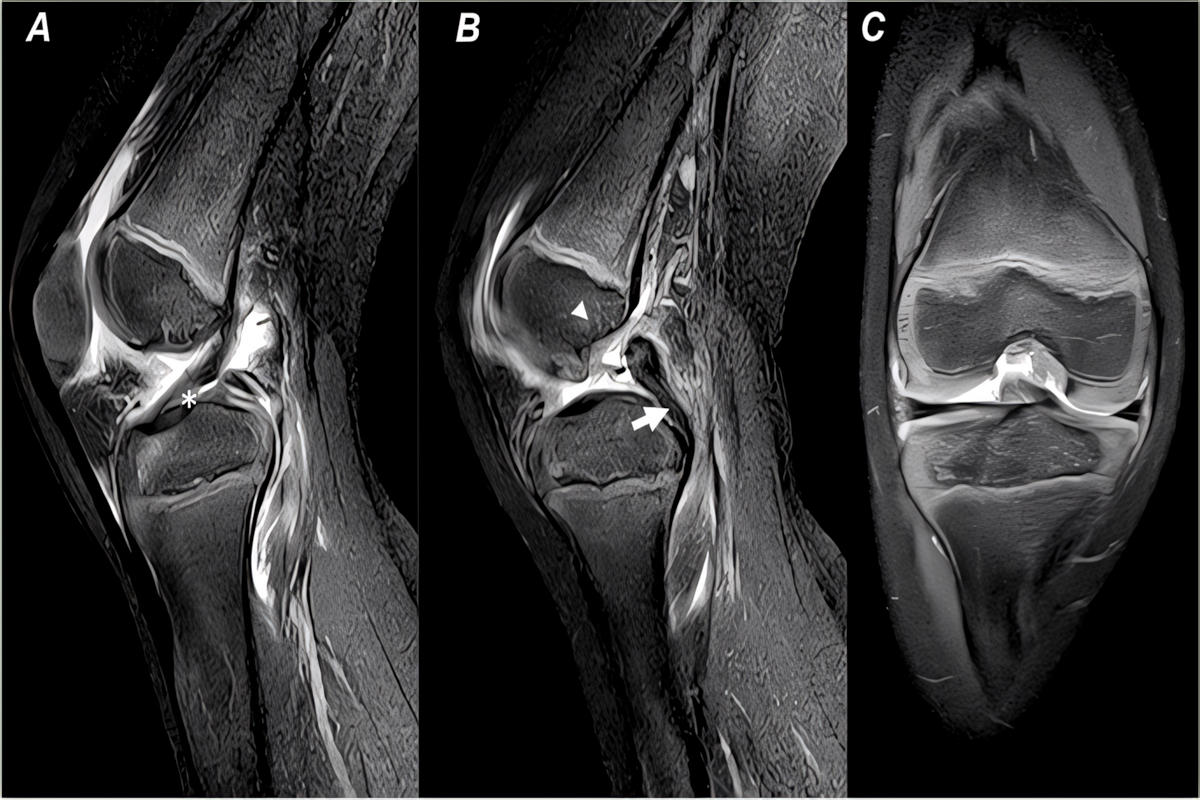

Απεικονιστικά, οι ακτινογραφίες είναι χρήσιμες για αποκλεισμό καταγμάτων. Η μαγνητική τομογραφία (MRI) αποτελεί τη μέθοδο εκλογής, καθώς επιβεβαιώνει τη ρήξη, εκτιμά τη βαρύτητα και ελέγχει για συνοδές κακώσεις. Σε χρόνιες ή σύνθετες περιπτώσεις, η αξονική μπορεί να βοηθήσει σε ειδικές οστικές εκτιμήσεις και σχεδιασμό.